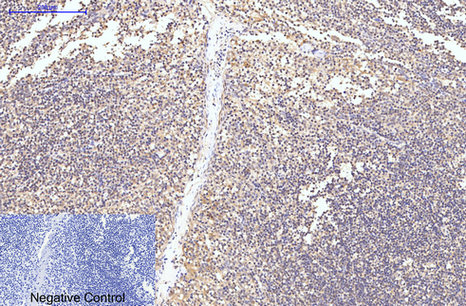

Immunohistochemical analysis of paraffin-embedded Mouse Spleen Tissue using Caspase-8 Monoclonal Antibody.